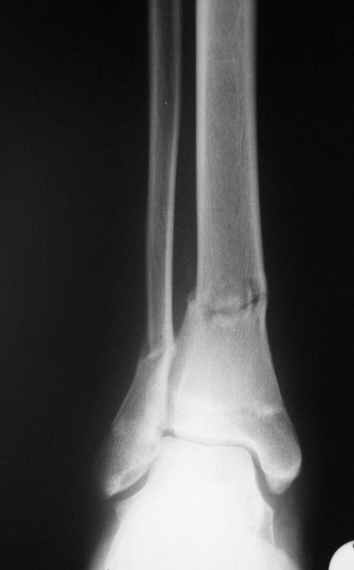

Уважаемые коллеги,Больной 17 лет , 3 недели с момента травмы, был переведен в наше отделение из соседнегогоспиталя.

Попытка закрытой ручной репозиции, предпринятая ранее в этой больнице,оказалась безуспешной, что и явилось причиной перевода к нам.Чтобы вы предложили в данной ситуации?Показана ли фиксация перелома малоберцовой кости в данном случае или в этом нет необходимости?Евгений Чекашкин

На прямой проекции видно угловое смещение отломков малоберцовой кости, обуславливающий и

наклон тарана, да и вальгус отломков б.б. , а на боковой проекции -смещение отломков

кпереди и по длине.

Коррекция углового смещения и смещения по длине отломков м.б. кости автоматом устраняет

наклон тарана , что необходимо для нормальной функции голеностопа. Так оно и произошло во

время операции.

Единственный момент, о котором я и уже писал - не наступило спонтанной анатомичной

репозиции отломков б.б., поэтому после репозиции пришлось использовать тягловый винт и

*укрепить* достигнутое положение узкой пластиной динамической компрессии.

Послеоперационные снимки сегодня посмотрел - все выглядит вполне анатомично, кроме длины

винтов на м.б. кость - слегка переборщил:-(( Не было камеры с собой , но как только

пересниму картинки обязательно вышлю.

Поэтому фиксация м.б. кости все-таки показана....